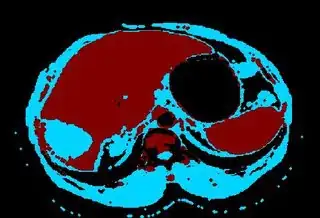

Below I apply two successive morphological openings to the image using a 3x3 circular kernel, and then apply k-means clustering to the gray levels. From your sample images and some I found on the internet, I decided to set k = 4. If you are using high-resolution images, first downsample them to dimensions ~400-600. Otherwise the morphological operation may not have a significant effect, and the k-means will be slow.

Below are some of the opened and segmented images. Of course there's more to be done in terms of

- separating out the liver region

- generalizing this to a large dataset

but hope this is at least a starting point.

You might be able to narrow down the region or interest by filtering out the darkest and the lightest regions from the segmented image. For this, use the k-means cluster centers, check for the extreme values (max and min) and remove the corresponding k values from the labeled image. Then you can look for large structures to the left of the result image. Worst case, you might get a hole on the left side when the extreme region filtering goes wrong. I've updated the code and results.